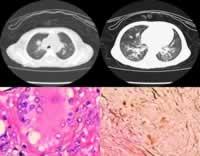

正常肝臟中此酶的活力最高,肝、腎、腦小腸亦富於此種酶。此病患者的肝、脾等組織中酶的活力降低至50%以下。患兒全身網狀內皮系統中可查見富含脂類的直徑為20~90μm的大型泡沫細胞,以脾、骨髓、肝、肺和淋巴結等部位為主。這種泡沫細胞又稱為尼曼-匹克細胞,通常僅見一個偏位的小細胞核,染色質疏鬆;胞漿充滿脂類小滴(胞質體),在未染色片上呈“桑葚”狀,Giemsa染色時,胞漿呈藍或藍綠色,內有深淺不一的藍色顆粒。不同於Gaucher細胞的是:酸性磷酸酶染色呈弱陽性;Schultz反應(檢測膽固醇)呈陽性。亦可用位相顯微鏡或電鏡檢查鑑別兩者。

尼曼匹克氏病臟器結果(A型或嬰兒型):為典型的尼曼-匹克(占85%),多在生後3~6月內,少數在生後幾周或1歲後發病。初為食欲不振、嘔吐、餵養困難、極度消瘦,皮膚乾燥呈臘黃色,進行性智力、運動減退,肌張力低軟癱,終成白痴,半數有眼底櫻桃紅斑(cherryred spot)、失明,黃疸伴肝脾大。貧血、惡液質,多因感染於4歲以前死亡。皮膚常出現細小黃色瘤狀皮疹有耳聾。神經鞘磷脂累積量為正常的20~60倍,酶活性為正常的5~10%,最低<1%。

尼曼匹克氏病肝脾腫大(C型慢性神經型):多見兒童,少數幼兒或少年發病。生後發育多正常,少數有早期黃疸。常首發肝脾腫大,多數在5~7歲出現神經系統症狀(亦可更早或遲到青年期)。智力減退,語言障礙,學習困難,感情易變,步態不穩,共濟失調,震顫,肌張力及腱反射亢進,驚厥,痴呆,眼底可見櫻桃紅斑或核上性垂直性眼肌癱瘓。可活至5~20歲,個別可活到30歲。SM累積量為正常的8倍,酶活性最高為正常的50%,亦可接近正常或正常。

5、肝、脾和淋巴結活檢均有成堆、成片或瀰漫性泡沫細胞浸潤。神經鞘磷脂。